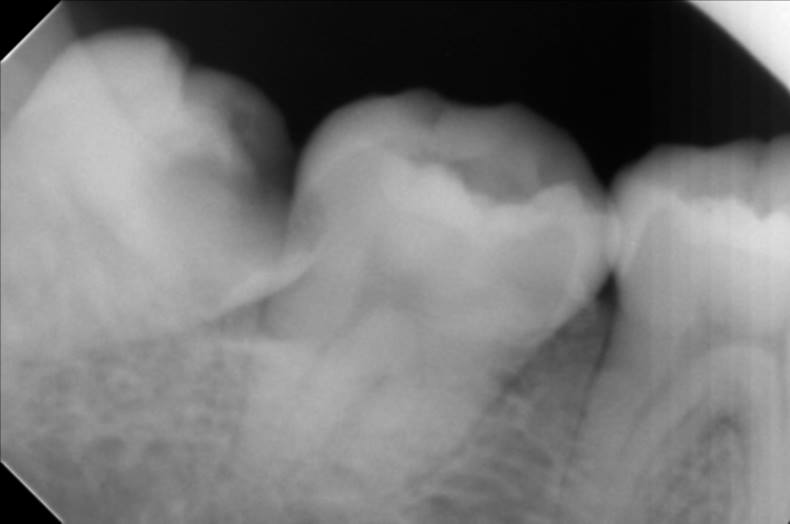

Răng khôn mọc lệch 45 độ là một trong những trường hợp xảy ra phổ biến khi mọc răng khôn. Khi bị răng khôn mọc lệch 45 độ nếu không xử lý có thể sẽ ảnh hưởng đến chức năng ăn nhai, ảnh hưởng đến chất lượng cuộc sống cũng như sinh hoạt hàng ngày của bạn. Vậy khi có răng khôn mọc lệch 45 độ chúng ta nên làm gì, mời các bạn theo dõi bài viết dưới đây nhé.

Răng khôn mọc lệch 90 độ là một trong những trường hợp không hiếm xảy ra. Răng khôn mọc lệch 90 độ thường gặp gặp với biểu hiện răng mọc lệch về phía răng số 7, mặt nhai răng 8 tiếp xúc với thân răng số 7. Răng số 8 mọc lệch hoàn toàn không có chức năng ăn nhai mà còn có thể gây ra khá nhiều biến chứng gây hại cho sức khỏe răng miệng và cả sức khỏe toàn thân.

Răng khôn là chiếc răng cối thứ 3 thường mọc độ tuổi từ 16 đến 26, răng khôn theo thuật ngữ y học gọi là răng số 8. Trên thực tế răng khôn mọc ngầm gây ra rất nhiều tác hại. Răng khôn không phải lúc nào cũng mọc đúng chỗ, đúng vị trí. Vì nó mọc sau cùng, mọc lên khi tất cả các răng khác đều mọc xong nên răng khôn hay bị mọc ngầm gây ảnh hưởng đến răng số 7, mọc ngầm gây viêm lợi.